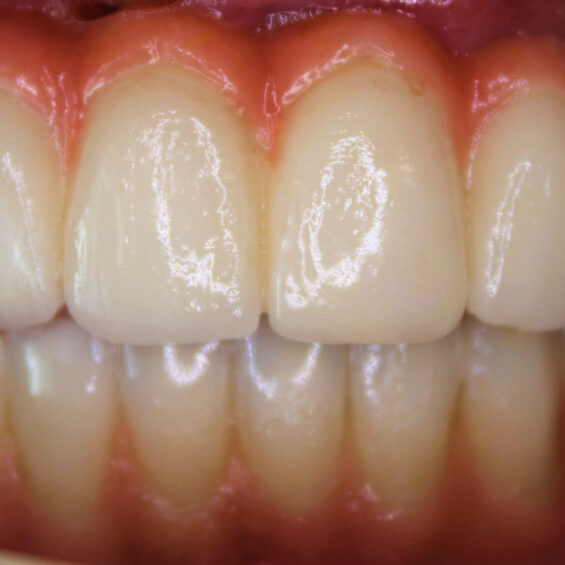

Decidí acudir ya que no aguantaba el dolor que tenía, no podía comer y me afectaba en el día a día. Cuando Susana me exploró, inmediatamente supo lo que necesitaba. Los dientes que me quedaban no podían aguantar más tratamientos Planificó la extracción de todos ellos y el tratamiento de All On Four superior y 6 implantes mandibulares . Con colocación inmediata de dientes el mismo día que me los extrajo y colocó los implantes. Entrar y salir con dientes.

Me ha cambiado la vida, estoy de maravilla. Ahora me paso el día enseñando los dientes, todos los problemas que tenía antes ya no los tengo y estoy muy contento.

Valentín ha sido en todo momento un paciente comprensivo y colaborador. Su cirugía requirió una planificación muy precisa, pues se trataba de implantes postextracción y carga inmediata. Finalmente, una rehabilitación fija sobre implantes con todos los criterios que exigía.

- Rehabilitación completa sobre implantes